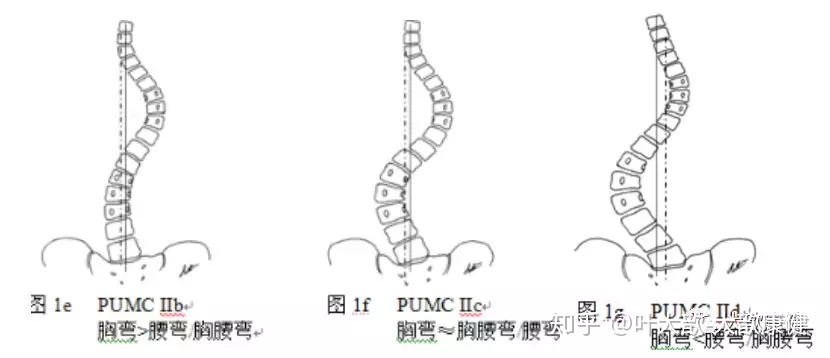

顶椎上在t3,t4,下在t11,t12;体征会有明显的高低肩,高低背,肩胛骨高低

上图:手术后:通过截骨切除半椎体,钉棒系统矫形固定,侧弯获得完全矫正